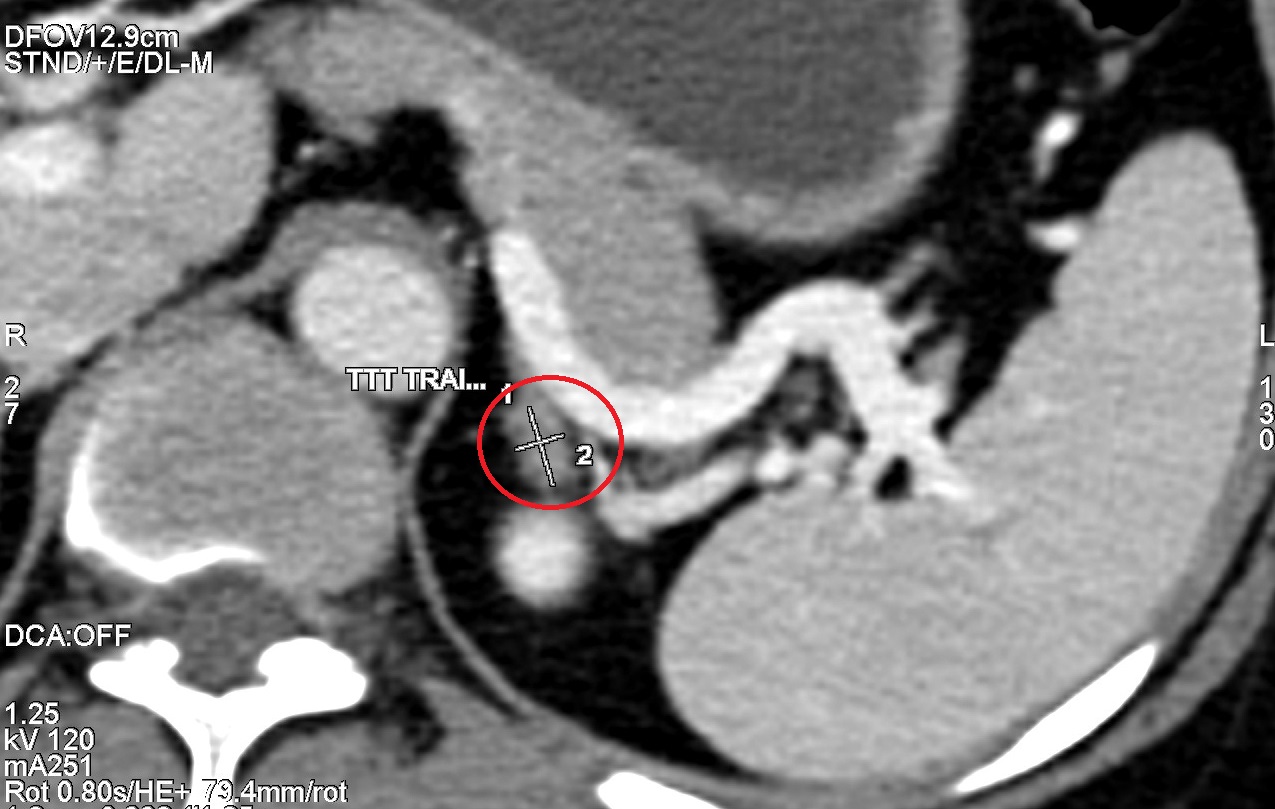

Trong một lần tầm soát định kỳ tại phòng khám Hương Sơn, bệnh nhân M.T.T (53 tuổi, Bình Đình) được chỉ định chụp CT toàn thân bằng công nghệ CT 2560 lát cắt hiện đại. Kết quả bất ngờ khi phát hiện:

Tuyến thượng thận trái có khối u kích thước 10mm, nghi ngờ mắc Adenoma tuyến thượng thận – một bệnh lý hiếm gặp, có thể dẫn đến cao huyết áp, suy tuyến thượng thận hoặc bệnh Addison.